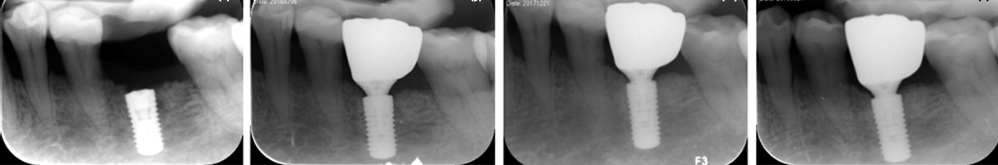

此外,该研究团队针对接受牙槽嵴保存术并完成种植修复的位点进行随访观察,首次对罹患重度牙周病变磨牙拔牙同期实施牙槽嵴保存后的种植修复效果进行评价,证实应用牙槽嵴保存术后种植修复体可维持长期健康稳定,这一结果对牙槽嵴保存的临床应用有十分重要的意义。该研究成果再次发表于《临床口腔种植学研究杂志》(Clinical Oral Implants Research),关键照片被选为2022年7月刊杂志封面(DOI: 10.1111/clr.13949)。

接受拔牙同期牙槽嵴保存术的患者种植手术后即刻、种植修复后1年、2年、3年随访X线片,种植体边缘骨水平稳定,证实牙槽嵴保存术后种植修复体可维持长期健康